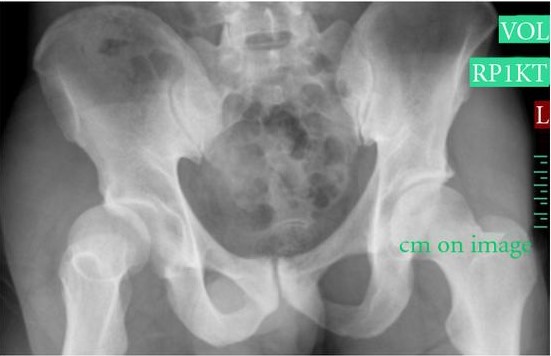

Bệnh nhân nam 38 tuổi tiền sử khỏe mạnh bị trật khớp háng (phải) về phía trước. Tai nạn xảy ra sau khi bệnh nhân sút bóng bằng chân phải, trong tư thế khớp háng phải xoay ngoài. Anh ta cảm thấy tiếng “pop” và ngã sấp. Sau tai nạn chân phải không thể chịu lực. Bệnh nhân khai không có va chạm với cầu thủ khác. Khám lâm sàng thấy chân phải xoay ngoài, không có điểm đau chói. X-quang xương chậu (thẳng) cho thấy trật khớp háng phải

Chụp X quang xương chậu thẳng cho thấy hình ảnh trật khớp háng (Phải)